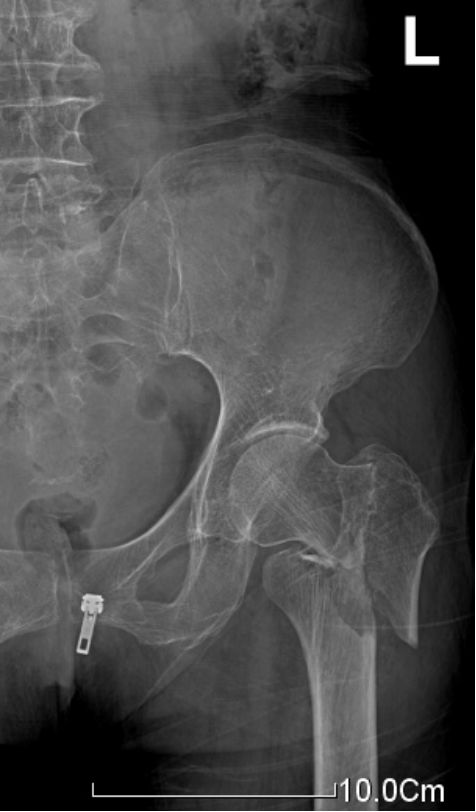

反转子间骨折

对于不稳定骨折,髓内固定的力学性能更好,力臂更短,术后器械相关并发症如股骨头切割、髋内翻、短缩和内固定物松动断裂概率更低。

适用于几乎所有的转子间骨折,特别适合于不稳定型骨折(如反转子间骨折)及合并骨质疏松者。